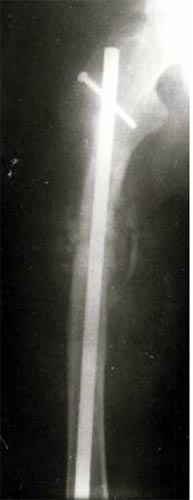

病例二、患者62岁,股骨中1/3骨折骨不连2年,3次钢板手术失败,明显畸形。

同上述方法治疗,9个月后骨折愈合。